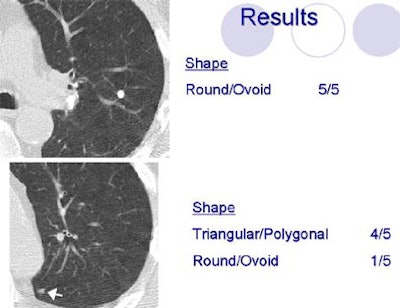

"Lung nodules seen on CT are often characterized by their size, shape, margin, and their attenuation," she said. However, because interobserver variability in determining these characteristics may affect diagnostic accuracy, the group conducted a study to assess variations among readers. They recruited five board-certified thoracic radiologists for the task, who were provided with visual training in nodule descriptors.

Shapes defined as "round/ovoid" or "triangular/polygonal" showed a fair amount of agreement, (k=0.31 and k=0.34, respectively), while evaluations of "lobular," "ill-defined" and "other" shapes had poor agreement. Agreement was also poor for the margin descriptors (smooth, spiculated, serrated, poorly defined or other) with kappa values under 0.2.

![]() |

| Radiologists' descriptions of lung nodules varied widely depending on the attribute. All images courtesy of Sara Rogers, MS. |

There was little agreement about nodules of mixed attenuation and generally poor interobserver agreement regarding shape and margin characteristics, Brown concluded. Poor agreement on such subjectively obtained nodule characteristics "may affect the ability to use these measurements in correlative studies of malignancy rates" among different types of nodule, she said.